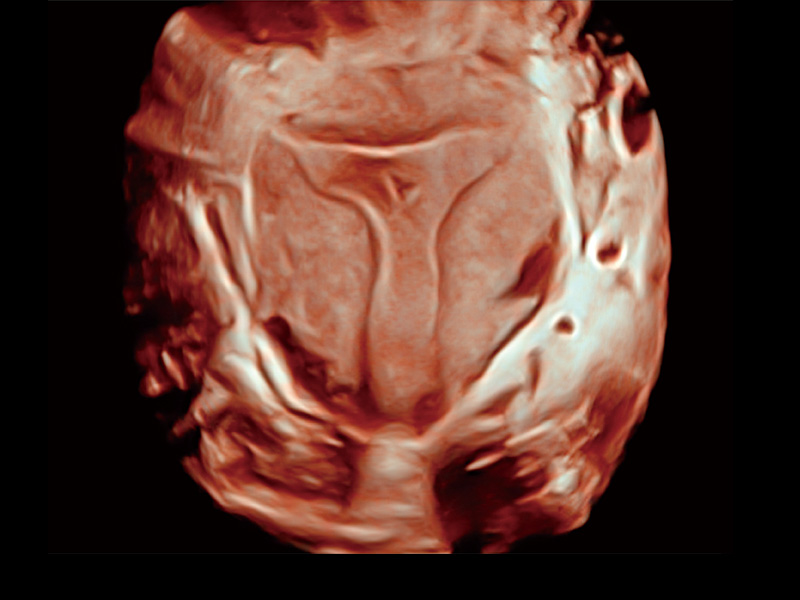

腔内容积探头

腔内三维成像技术获得显著提升,超大扇角在满足日常基础扫查的同时,支持卵泡自动测量及多种三维渲染模式,为您提供更多的诊断信息,尤其是在子宫畸形的诊断,内膜及肿瘤占位观测中起到了重要的作用。

单角子宫